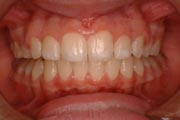

Crowding

After